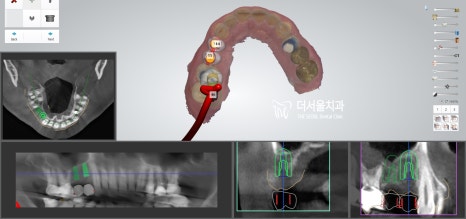

디지털 방식의 분석을 이용하여

식립 방향 및 각도를 결정하고

최종적으로 심어질 위치까지 선정했습니다.

이후 계산된 곳에 튼튼한 픽스처를 심어드렸죠.